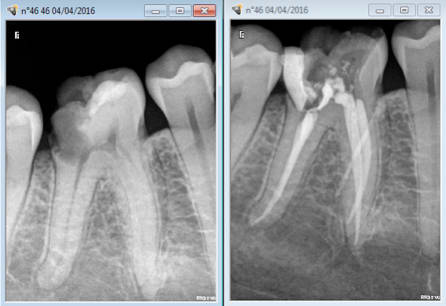

Je reviens sur ce cas à l'image curieuse. patient venu en urgence et je m'étais démerdé pour faire le TT en un RDV quitte à modifier quelque peu mon planning de la journée ( léger retard).

Rendez vous dans un an en urgence pour l'extraction. Que j'adresserais au stomato. -)

Et là, un gros canal latéral ou un coup de pro-taper retraitement mal placé ??